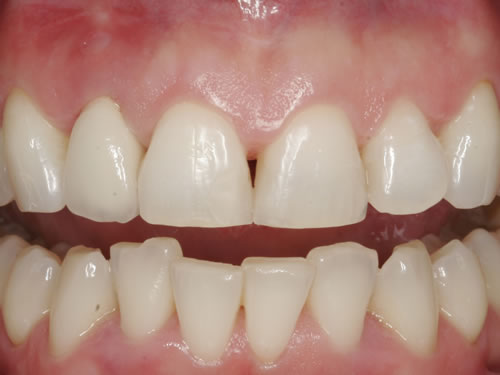

Eine besondere Herausforderung ist die Oberkieferfrontzahnregion. Der Wunsch nach einem perfekten Resultat ist geradezu selbstverständlich. Jeder möchte große, weiße Zähne und ein gesundes, reizloses Zahnfleisch besitzen (Abb. 3.30).

Abb. 3.30: Perfektes Resultat einer Versorgung.